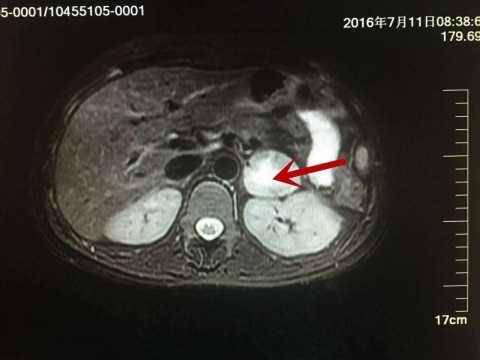

市五医院以微创技术成功为孕妇实施肾上腺嗜铬细胞瘤切除术

8月30日上午,复旦大学附属上海市第五人民医院施国伟主任率领泌尿外科团队在妇产科、内分泌科、麻醉科、